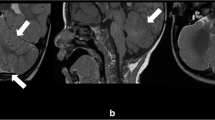

This male infant was vaginally delivered after induction, following 38 weeks of gestation (by dates), to a 27-year-old, gravida 3, para 1 (2 spontaneous abortions), mother. There is no known history of congenital abnormalities in the family. At 27 weeks of gestation, an ultrasound examination of the fetus revealed dilatation of the fourth ventricle and absence of the cerebellum. Subsequent ultrasound examinations at 30 and 36 weeks of gestation revealed intrauterine growth retardation consistent with 29 weeks gestation, without further fetal growth, and a Dandy-Walker abnormality as well as hydrocephalus. Prenatal laboratory testing of the mother was unremarkable. At birth, the baby was intubated due to respiratory insufficiency. Birth weight was 2,100 g. The head was microcephalic (circumference 27 cm) with small anterior and posterior fontanelles and closed sutures. The baby moved all extremities with appropriate muscle tone but had diminished reflexes in his upper and lower extremities. On the second day of life, magnetic resonance imaging (MRI) of the head (Fig. 1) confirmed severe brain malformation. The infant died 7 days after birth. Chromosomal analysis on the patient’s blood revealed a normal male karyotype (46, XY). Fluorescence in situ hybridization (FISH) chromosomal analysis did not detect deletions in the DiGeorge and Miller-Dieker critical regions. Gene analysis of reelin (RELN) was not available.

MRI of the head confirming near total absence of the cerebellum with prominent cystic dilatation of the fourth ventricle (A, B), consistent with Dandy-Walker syndrome. The cerebrum shows complete lack of gyral formation (lissencephaly), with a thin continuous zone of T2 hypointensity in what seems to be the subcortical area (arrowheads in B, arrows in D), bilaterally. Note a thickened calvarium (asterisk in A), hypoplastic cerebellum (arrows in B), agenesis of the corpus callosum (C), hypoplastic brainstem (arrow in A), basal ganglia and thalami (A, C), and undulating ventricular surface (arrowheads in C, D). A: T1-weighted image, sagittal, B,C: T2-weighted image, coronal, D: T2-weighted image, axial

Recently, six categories of LCH (LCHa–f) have been proposed mainly based on the neuroradiographic findings [44]. Of note, two pediatric cases are listed as a heterogeneous group of agyria/pachygyria associated with absent corpus callosum, moderate to severe cerebellar hypoplasia and brainstem hypoplasia of unknown inheritance (LCHf in the series). One presented with complete agyria and severe hypoplasia of cerebellum and brainstem, and had a thin continuous band of high signal intensity on T2-weighted sequences in what seems to be the subcortical area, as well as focal undulation of the ventricular surface—almost identical to that observed in MR images of the present case (Fig. 1). Mutations in LIS1 can also cause a LCH phenotype (LCHa) that displays mild vermian hypoplasia, lissencephaly with either an anterior-to-posterior or posterior-to-anterior gradient of severity, and presence of the corpus callosum, even if it is hypoplastic—the features do not match those in the present case. Furthermore, in the recent classification of cerebellar malformations, a heterogeneous group of lissencephaly with cerebellar dysplasia has been proposed, listing three cases in a series of 70 MRI studies obtained in patients with cerebellar anomalies [39]. Apart from one case with a RELN mutation, the other two cases without known gene mutations were associated with agenesis of the corpus callosum, small-sized brainstem and tiny cerebellar hemispheres with no visible vermis, implying similar anatomical features to those in the present case. However, there has been neither a detailed histopathological verification nor an immunohistochemical characterization of LCH reported.

A four-layered neocortical structure is, together with preserved superficial marginal layer, a characteristic histological abnormality that distinguishes type I from type II lissencephaly [18, 35]. MRI-neuropathological correlations in the present case revealed that the band of high T2 signal represents the MRI counterpart of a sparsely cellular layer, as has been previously suggested [28]. Hence, the presence of this T2 high intensity band is predictive of a histological four-layered cortex typical of type I lissencephaly, at least in the developing brain.